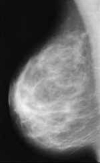

onkologische Mamma-Diagnostik - Nachsorge incl. Biopsie und Galactographie